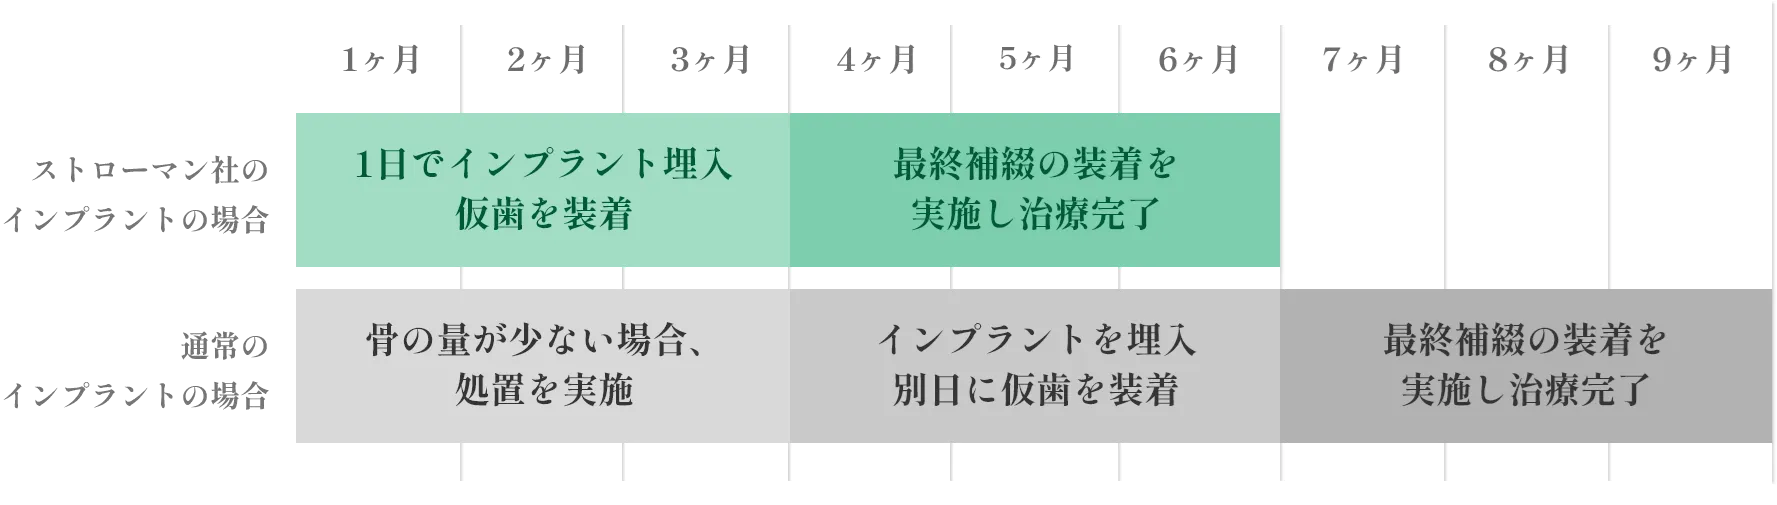

ストローマン社製のインプラントなら、

治療期間を通常より3ヶ月短縮でき、

負担を軽減してインプラント治療を

行えます。